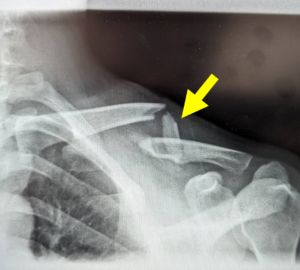

写真:高度の転位と第三骨片(黄矢印)を伴う鎖骨骨幹部骨折、患者より提供